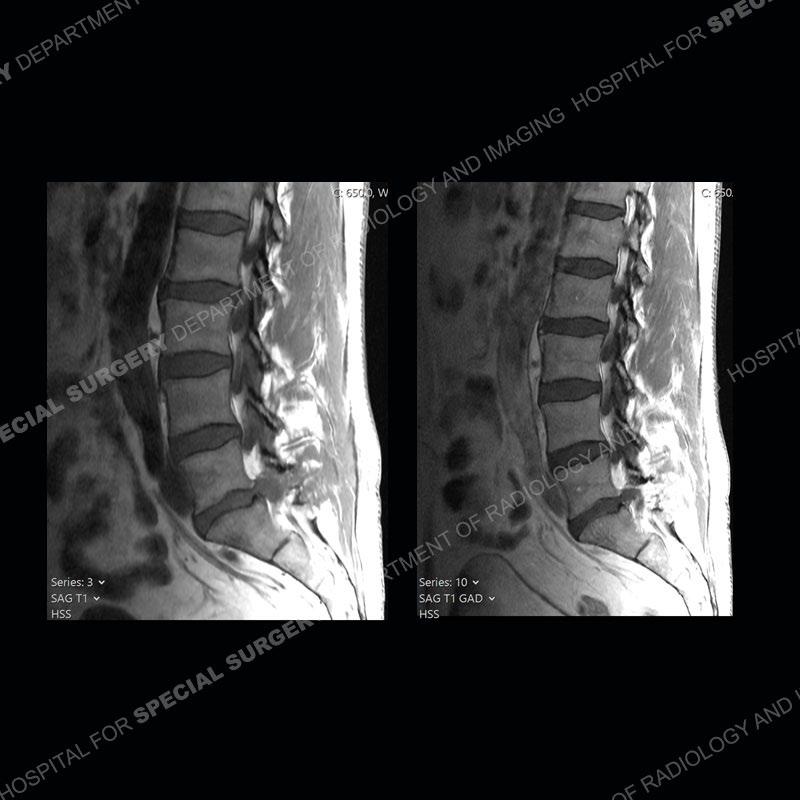

Post operative changes are seen on the left side at L5-S1 where there is near complete removal of the left sided L5 lamina, partial resection of the left L5-S1 facet joint, and resection of the left sided ligamentum flavum. In the anterolateral epidural space about the subarticular recess is a mass that demonstrates similar T1 and T2 signal characteristics to the adjacent degenerated disc. There is enhancement about the periphery of the mass, but the majority of this somewhat geographic or polyploid mass demonstrates no enhancement. The mass exerts prominent mass effect on the left S1 axillary sleeve/proximal nerve root. The left S1 nerve root shows enlargement and increased enhancement as compared to the contralateral right side.

Diagnosis: Recurrent Disc Herniation

Not as much of a diagnostic dilemma as some other cases but more so just a very nice example of what can be a difficult assessment at times. The evaluation of granulation tissue/scar/epidural fibrosis vs. disc herniation particularly in the earlier post operative period can be very difficult. Clues that can assist in identifying a disc herniation are a more geographic or polypoid nature to the mass, signal characteristics similar to the adjacent degenerated disc, mass effect upon the thecal sac/adjacent neural structures, and a typical enhancement pattern. As the disc material is avascular, as long as imaging is performed in a relatively rapid fashion after contrast administration (within 20-30 minutes), the granulation tissue around the disc will enhance but the disc material itself will not. If there is a marked delay between contrast administration and imaging, there may be diffusion of contrast into the disc making the assessment very difficult. The marked utility of contrast to help delineate disc vs. scar has led to our institution employing contrast fairly uniformly within the first two years following surgery.